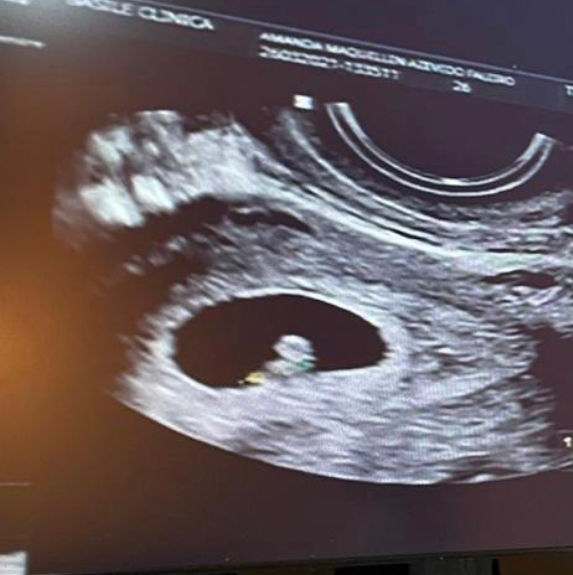

E foi com o intuito de não preocupar seus fãs que escondeu, atrás de sorrisos que não eram reais, a verdadeira história do momento que estava passando. Sofreu uma interrupção espontânea de uma gravidez de quase três meses apenas três semanas depois que recebeu a notícia da gestação.

Por ser uma gravidez de risco, a influencer precisou esconder a gestação do seu público para proteger seu bebê. Todo sigilo era necessário para o bem estar dela e da sua gestação. Era um momento complicado e tinha receio até de criar expectativas.

Mas infelizmente a gestação foi interrompida involuntariamente de forma agressiva. A modelo ficou dois dias internada em um hospital passando por procedimentos de curetagem realizado com o objetivo de limpar o útero através da remoção de restos de um aborto incompleto.